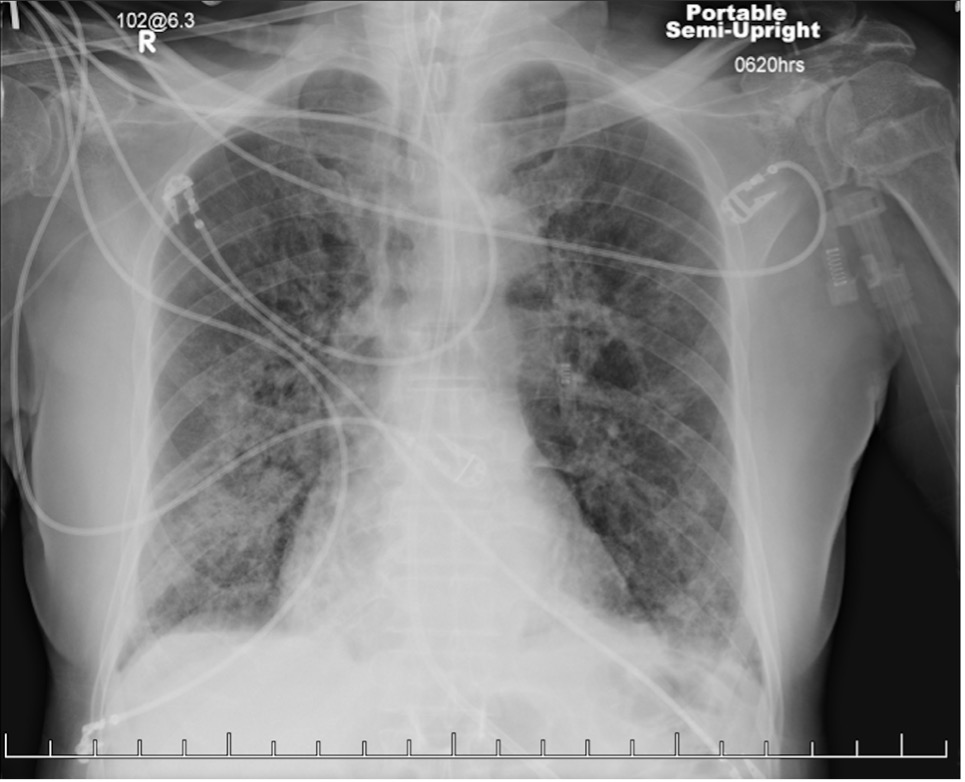

Reassessment of the patient’s presentation and findings resulted in a differential diagnosis of cryptogenic organizing pneumonia (COP). The patient was given intravenous methylprednisolone, 1 mL/kg/d, and had significant improvement of his respiratory symptoms within 24 hours. Serial chest radiographs taken at follow-up demonstrated partial resolution of infiltrates compared with previous imaging studies (Figure 3).

Figure 3. Chest radiographs taken 1 week (a, top) and 2 weeks (b, bottom) after initiating intravenous glucocorticoid therapy. The patient had been extubated and demonstrated significant improvement of symptoms during this period.Discussion. COP is a rare idiopathic interstitial lung disease that requires surgical biopsy for confirmation.1,2 In scenarios in which a biopsy is unavailable and the patient is intubated—such as in our case—careful consideration is needed. Adverse effects of glucocorticoids in a critically ill patient include immunosuppression and increased risk for potentially fatal nosocomial infection.3 Trial therapy should be started only if other, more common diagnoses have been excluded and if imaging studies are consistent with COP or another inflammatory process, such as acute respiratory distress syndrome. Fortunately, in our case, radiograph and CT findings did feature lower lobe consolidation and infiltration described in other reports of COP.3,4 Once suspicion for COP is high, the patient should be consulted on the risks of surgical lung biopsy vs trial glucocorticoid therapy and be offered a choice in which step to take next.